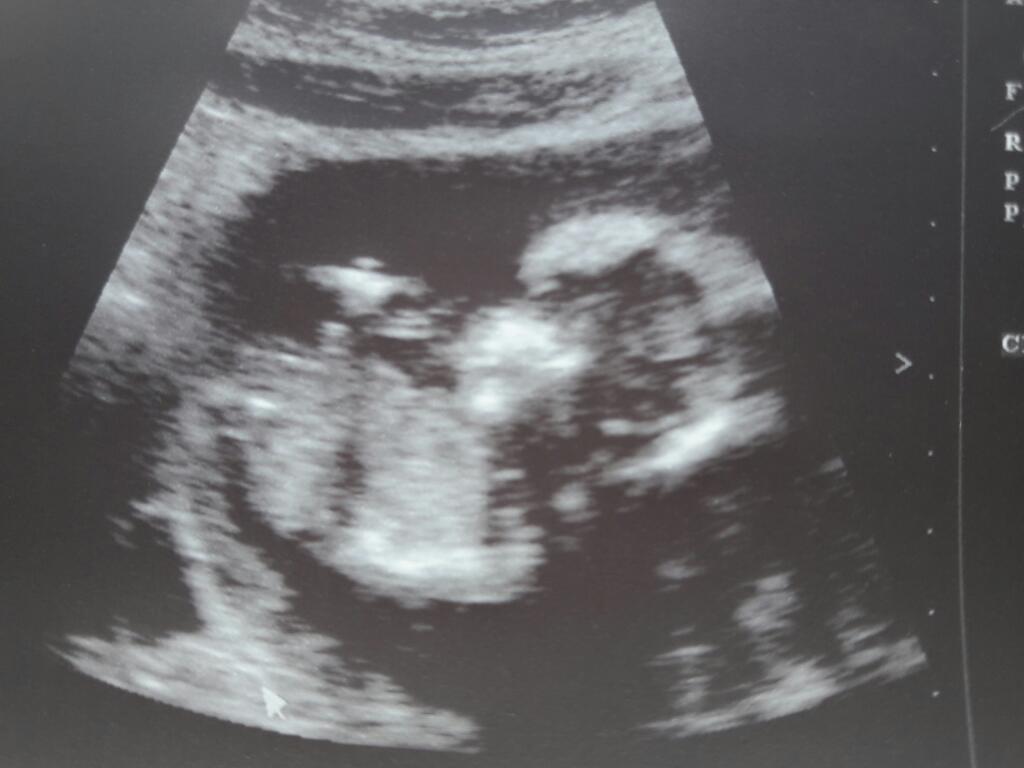

Mój lekarz był za to bardzo uprzejmy :-)

Długo mnie oglądał, wszystko mierzył i opowiadał, nawet bardziej szczegółowo niż na prenatalnych, ale wtedy był w szpitalu na dyżurze i nie miał czasu.

Śmiałam się, ze siurka widzę, a on że "mamie to tylko seks w glowie" , potem coś męża zapytał, a ten coś żartem mu odpowiedział i zaczął lekarz się śmiać ze porządnie wyposzczeni jesteśmy, ale z przykrością musi powiedzieć, że jeszcze nie odwołuje zakazu seksu... ;-)

Zaraz zmniejszam rozmiar zdjęć i wstawię dzidzie i dzisiejsze zakupy ;-)

Hej. Ale mnie trzymał i o siebie ten doktorek, ponad 40 minut! Ale tak mnie przeswietlil ze nawet na prenatalnych się tyle od niego nie dowiedziałam co dziś. Z dzidzia wszystko dobrze, wszystko ma na miejscu i nic jej nie brakuje :-) wody w normie, dziecko ma miejsce, żeby się obracać ;-) odklejac mi sie łożysko.. . Kazał się bardzo oszczędzać... no i mam bardzo liczne bakterie i leukocyty leukocytów w moczu, morfologia też trochę słabo wyszła... Kazał zrobić posiew i morfologia z przeciwcialami na cito. I mam jakaś infekcje.

Dziewczyny polecicie mi jakiegoś ginekologa w Katowicach gdzie zrobię usg? Chce poznać płeć dzidzi. Bo z ostatniego zdjecia to nic nie widac:(

d3bd5cc2de9648732e15c0561e68afe8.jpg